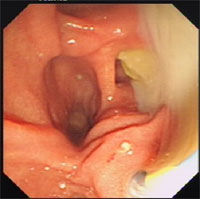

5.內鏡治療:各種內鏡治療方法有了很大的進展,針對原發性硬化性膽管炎來說,它在緩解阻塞症狀、改善生化功能及預防膽管炎發作等方面均有效果。相對於手術治療,它有幾個優點:手術相對簡單;診斷的同時可以進行治療;用一種方法擴張多處狹窄;能重複治療,對病人危險性小。但當病情發展到了晚期,出現肝硬化、門脈高壓、肝性腦病時,通常不適宜做內鏡治療,除非是為了在肝移植前暫時緩解阻塞和改善肝功能。內鏡的長期療效有待更多的隨機試驗來證實,但就臨床報導來看,這一引流技術可以延緩原發性硬化性膽管炎的病程,為病人提供更好的生活質量。

常用的內鏡治療方法有:①內鏡下乳頭肌切開術:一般來講,這種方法常結合其他內鏡治療。乳頭肌切開是為了便於插入導管、擴張氣囊或內支撐管。單獨乳頭肌切開僅用於那些狹窄明顯、導絲不能通過或無法擴張放置內支撐管的病人。②膽道狹窄的內鏡下擴張:套用氣囊導管做內鏡下擴張治療原發性硬化性膽管炎首次報導於1983年。現有的氣囊導管由於採用了新的耐高壓材料,可使用高達30個大氣壓的壓力進行擴張。另外,也可使用分級同軸擴張導管進入膽道進行擴張。其直徑最大可達12F。這類擴張導管最適用於狹窄明顯、氣囊導管無法通過時,先用擴張導管進入狹窄部位,再引入氣囊導管,可使狹窄部位達到最大限度的擴張。由於原發性硬化性膽管炎的長期嚴重纖維化,擴張後狹窄再發生率很高,多數學者認為在擴張後宜放置內支撐管數月以維持管腔通暢。③經乳頭內鏡下放置內支撐管:自1980年以來,內鏡下放置內支撐管已成功地用於緩解惡性膽道梗阻,並逐漸用於其他良性膽道狹窄包括原發性硬化性膽管炎。放置內支撐管時要選用大直徑(10~12F)管以保持狹窄部位最大限度的擴張,並可防止阻塞。術後常規套用數天抗生素。一般在術後3~6個月,病人再次阻塞或黃疸症狀時,需及時更換支撐管或進行氣囊擴張。儘管有人認為放置內支撐管會增加膽管炎的發生率,但在高度狹窄的部位插入支撐管以防止慢性狹窄的產生,同時配合使用抗生素,在術中和術後一段時間內膽管炎發生的機會是不多的。④膽道灌洗:通過內鏡在膽道放置引流管(如鼻膽管),用皮質激素鹽水和抗生素鹽水交替灌洗,對部分病人也有不錯的療效。可能是因為這部分患者膽道狹窄的原因並非是重度的纖維化,而是水腫、炎症和潰瘍,通過灌洗可起到減少炎性滲出和抗炎的作用。一組採用鼻膽管灌洗、狹窄擴張和插入支撐管相結合方法,隨訪了42例病人(平均4.3年),除2例後來發現合併膽管癌而療效不明顯外,其餘40例血清膽紅素和鹼性磷酸酶平均下降80%和60%。雖然灌洗治療取得可喜的效果,但在技術上還是有些缺陷。首先療程較長(一般要14周),可能產生感染併發症;其次外引流使膽汁丟失,擾亂肝腸循環。